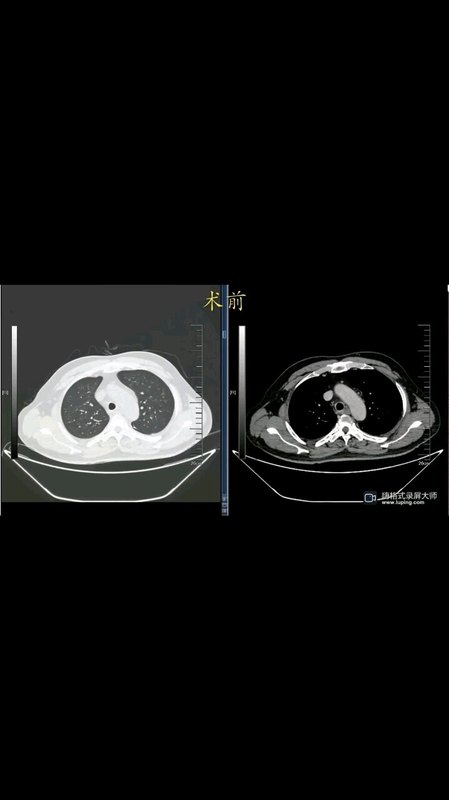

就問你,這樣吃雞刺不刺激?

廣東有句話叫“無雞不成宴”,沒有一盤雞的飯宴,那根本不是真正的飯宴。足見廣東人對吃雞的喜愛,白切雞、鹽焗雞、豉油雞、棟企雞、手撕雞、桑拿雞、啫啫雞、沙姜雞、椰子雞、豬肚雞,餐餐變著花樣吃雞,真是刺激。 但是吃雞如果不專心,很容易出現(xiàn)另一番刺激。 但是吃雞如果不專心,很容易出現(xiàn)另一番刺激。 5天前85歲的梁老漢吃雞時誤吞了雞骨頭,出現(xiàn)咽喉疼痛,胸部CT檢查提示雞骨頭卡在食管,而且已經(jīng)把食管扎穿了,由于風(fēng)險太大,當(dāng)?shù)蒯t(yī)院建議到我院就診。經(jīng)過與患者和家屬充分溝通,在胸外科保駕之下,急診行胃鏡檢查,胃鏡下可以看到一根雞骨頭牢牢地插在食管壁上,取出雞骨頭后可以看到明顯的食管穿孔、潰瘍形成。無獨有偶,僅隔一天,又遇到了一個34歲喜歡吃雞的老廣,由于吃雞時談笑風(fēng)生,把雞骨頭也吞了下去,過了數(shù)日開始出現(xiàn)胸痛后才趕來就診,胃鏡下取出雞骨頭時,同樣可以看到食管壁上被骨頭扎穿了一個洞。 據(jù)報道約1%-4%的食管異物會引起食管穿孔,除了與異物的尖銳程度有關(guān)外,這種情況多發(fā)生于誤吞異物后試圖采用進(jìn)食固體食物將食管異物推到胃里的患者或未及時就診的患者。像梁老漢誤吞雞骨頭3天后才到醫(yī)院就診,期間還在不停地吃吃吃,穿孔在所難免。這位年輕的老廣在誤吞雞骨頭快1周了才來就診,除了食管穿孔,胸部CT檢查時發(fā)現(xiàn)已有縱隔膿腫形成了,骨頭離主動脈只有幾毫米,取骨頭的過程非常危險,一不小心就要胸外科開胸手術(shù)。而且,這類患者并不是胃鏡下取出雞骨頭就萬事大吉了,他們術(shù)后都要禁食禁水、留置胃管進(jìn)行胃腸減壓,同時還要強(qiáng)力抗感染、抑制胃酸、空腸營養(yǎng)等,如果保守治療效果不佳的,還是要外科手術(shù)。這也就是為什么有些人誤吞個雞骨頭,卻要花費(fèi)數(shù)萬甚至更多的金錢來救治。許多患者這會才懊惱為何當(dāng)初沒有早點去醫(yī)院就診。 這樣吃雞夠不夠刺激? 也許,有些老廣會認(rèn)為為了吃雞,受點刺激,遭點罪也沒什么大不了的。但是吃雞時誤吞骨頭造成的傷害有時候遠(yuǎn)不止食管穿孔這么簡單,有些人甚至為此付出生命的代價。 為什么誤吞雞骨頭容易卡在食管呢? 成人的食管直徑僅約2cm左右,但是食管并不是跟水管一樣呈圓柱狀,它存在著3個生理性狹窄,分別在位于距離門齒15cm、25cm和40cm的地方,誤吞進(jìn)去的骨頭就很容易卡在這些狹窄的地方,尤其是第一狹窄處。 雞骨頭卡在食管會出現(xiàn)什么危害? 食管管壁柔軟且菲薄,一般厚度在3mm左右。因此誤吞雞骨后,尖銳的骨頭容易損傷管壁,造成食管黏膜糜爛\剝脫、食管出血、食管穿孔等。食管緊鄰縱隔,食管穿孔未及時處理,容易引起縱隔膿腫,處理不當(dāng)則會引起膿毒血癥,甚至有生命危險;食管緊鄰主動脈弓,一旦骨頭刺穿食管并損傷到主動脈弓,也很容易出現(xiàn)生命危險。 誤吞雞骨頭后,該怎么辦? 誤吞雞骨頭后不應(yīng)迷信土方法,企圖通過進(jìn)食饅頭、地瓜等塊狀食物將其帶入胃里,這樣只會加重對食管的損傷;企圖通過喝醋來軟化骨頭的方法也是不可取的。正確的方法是立即停止進(jìn)食,立即到有資質(zhì)的醫(yī)院就診。小編就曾遇到一患者,誤吞雞骨頭后,在家嘗試各種土方法,硬扛了1周也沒把骨頭擠到胃里去,最后出現(xiàn)胸痛、高燒了才到醫(yī)院就診,但是辦完住院不到幾個小時就出現(xiàn)大量嘔血,生命戛然而止。 說了這么多,并不是勸老廣們不要吃雞,只是吃雞的時候要當(dāng)心,畢竟誤吞了雞骨頭之后的刺激,有時候真的很驚心動魄。 好了,祝各位老廣們大吉大利,天天吃雞!